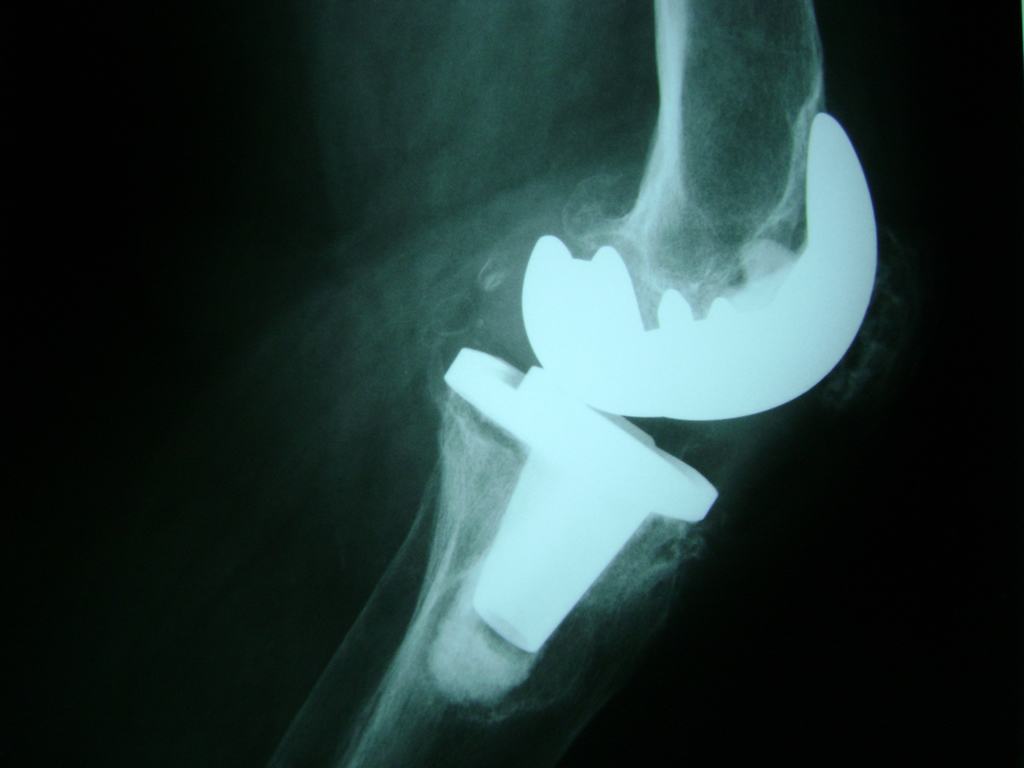

Cirugía de Fémur - Rodilla